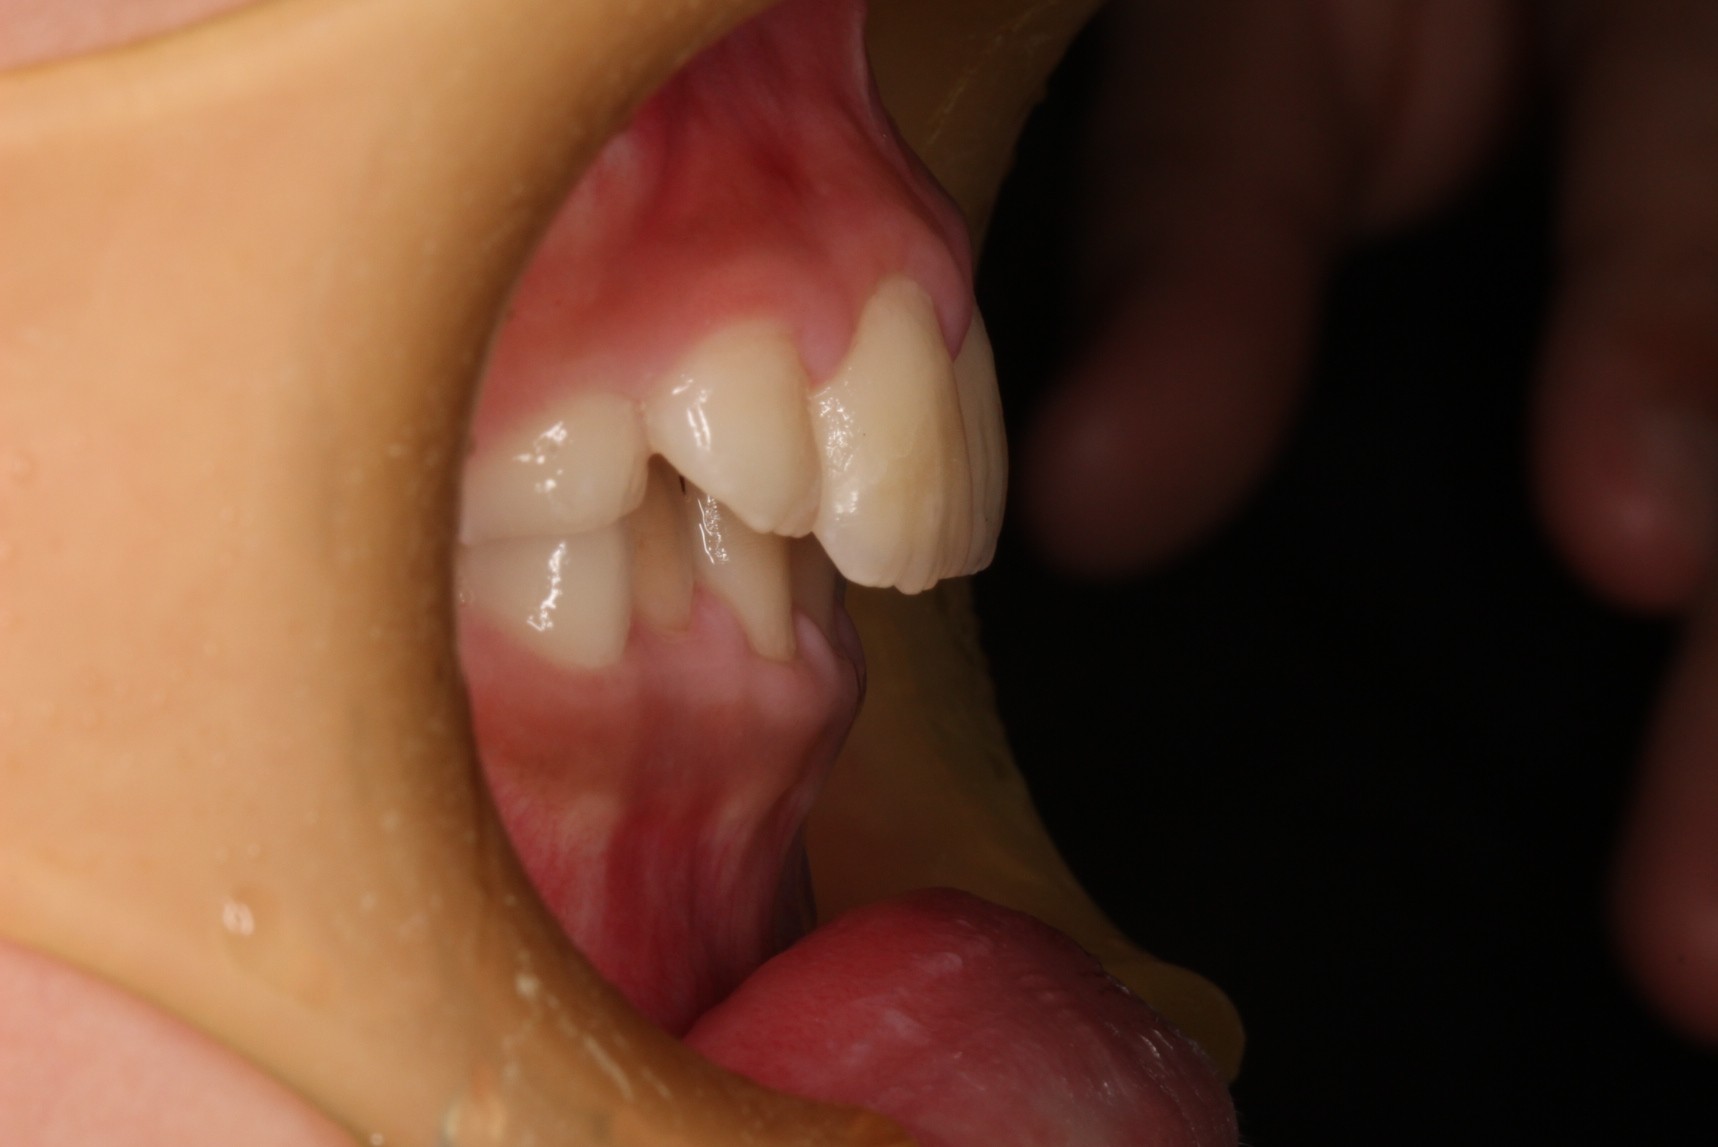

矯正術前:右側

矯正術後:右側